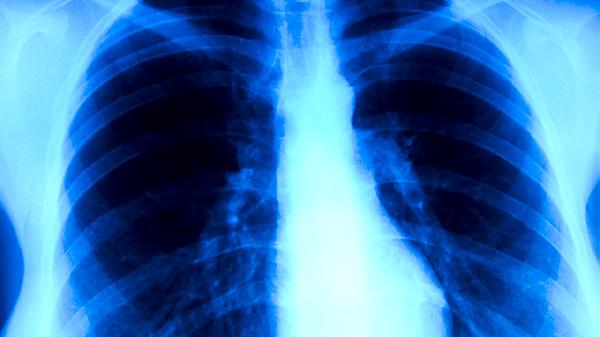

治療期間每1-2個月需進行痰涂片檢查、胸部X線或CT復查,評估病灶吸收情況和痰菌轉陰狀態(tài)。痰菌持續(xù)陽性者需調(diào)整用藥方案,治療6個月后未轉陰可能需延長療程至9-12個月。治愈標準需滿足臨床癥狀消失、影像學顯示病灶穩(wěn)定、痰菌連續(xù)3次陰性。糖尿病患者、HIV感染者等特殊人群需加強血糖控制和免疫狀態(tài)監(jiān)測。